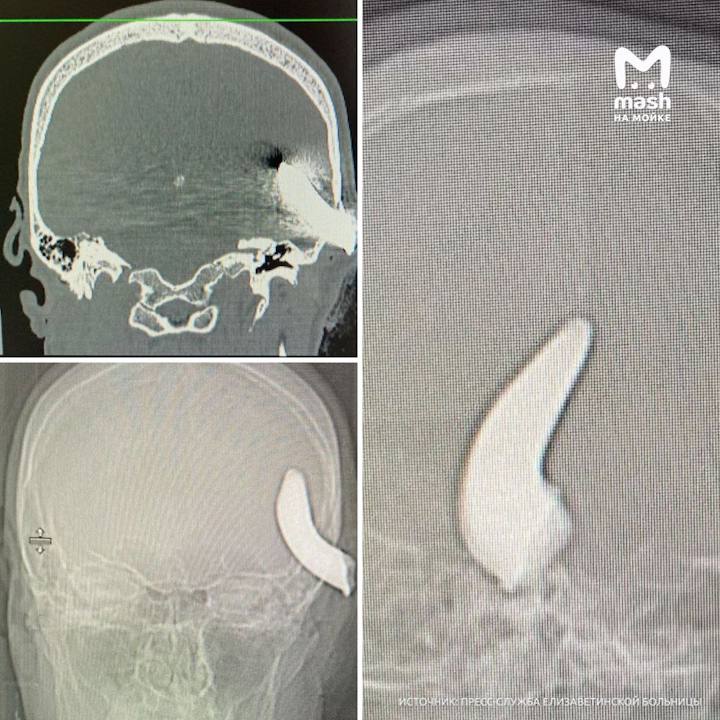

Металлический крюк длиной 6 см вынули из головы пациента Елизаветинской больницы — хирурги провели трёхчасовую операцию на мозге и тканях и смогли успешно устранить последствия неудачной буксировки машины.

36-летний Никита помогал другу во дворе перетащить его авто. Прицепили буксировочный трос, начали, но при движении фрагмент вдруг откололся и отскочил прямо в голову мужчине.

В больницу пациента привезли уже с признаками нарушения речи и движений в конечностях. Врачи диагностировали открытую черепно-мозговую с наличием инородного предмета и экстренно начали трепанацию черепа, сообщили в пресс-службе больницы.